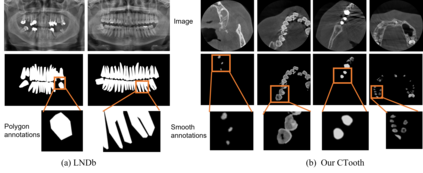

3D tooth segmentation is a prerequisite for computer-aided dental diagnosis and treatment. However, segmenting all tooth regions manually is subjective and time-consuming. Recently, deep learning-based segmentation methods produce convincing results and reduce manual annotation efforts, but it requires a large quantity of ground truth for training. To our knowledge, there are few tooth data available for the 3D segmentation study. In this paper, we establish a fully annotated cone beam computed tomography dataset CTooth with tooth gold standard. This dataset contains 22 volumes (7363 slices) with fine tooth labels annotated by experienced radiographic interpreters. To ensure a relative even data sampling distribution, data variance is included in the CTooth including missing teeth and dental restoration. Several state-of-the-art segmentation methods are evaluated on this dataset. Afterwards, we further summarise and apply a series of 3D attention-based Unet variants for segmenting tooth volumes. This work provides a new benchmark for the tooth volume segmentation task. Experimental evidence proves that attention modules of the 3D UNet structure boost responses in tooth areas and inhibit the influence of background and noise. The best performance is achieved by 3D Unet with SKNet attention module, of 88.04 \% Dice and 78.71 \% IOU, respectively. The attention-based Unet framework outperforms other state-of-the-art methods on the CTooth dataset. The codebase and dataset are released.